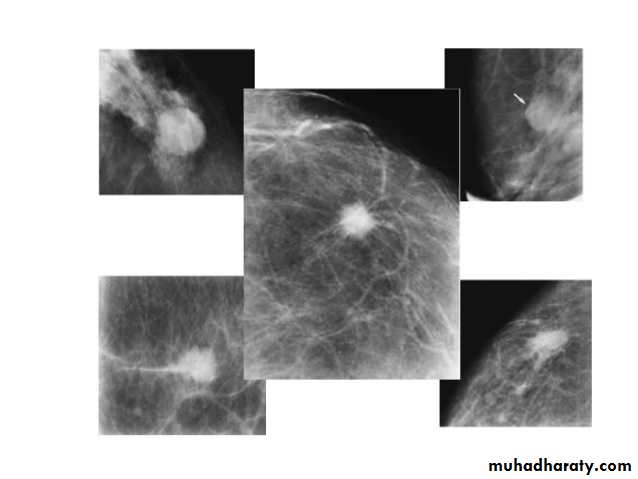

A…..Invasive ductal carcinoma is a subset of ductal carcinoma. It is an infiltrating, malignant and abnormal proliferation of neoplastic cells in the breast tissues. It is the most frequently seen breast malignancy .Radiographic features

Mammogramspiculated hyperdense lesion

oval/lobulated lesion

microcalicifications

Invasive ductal Ca invasive lobular CA

Micro calcifications